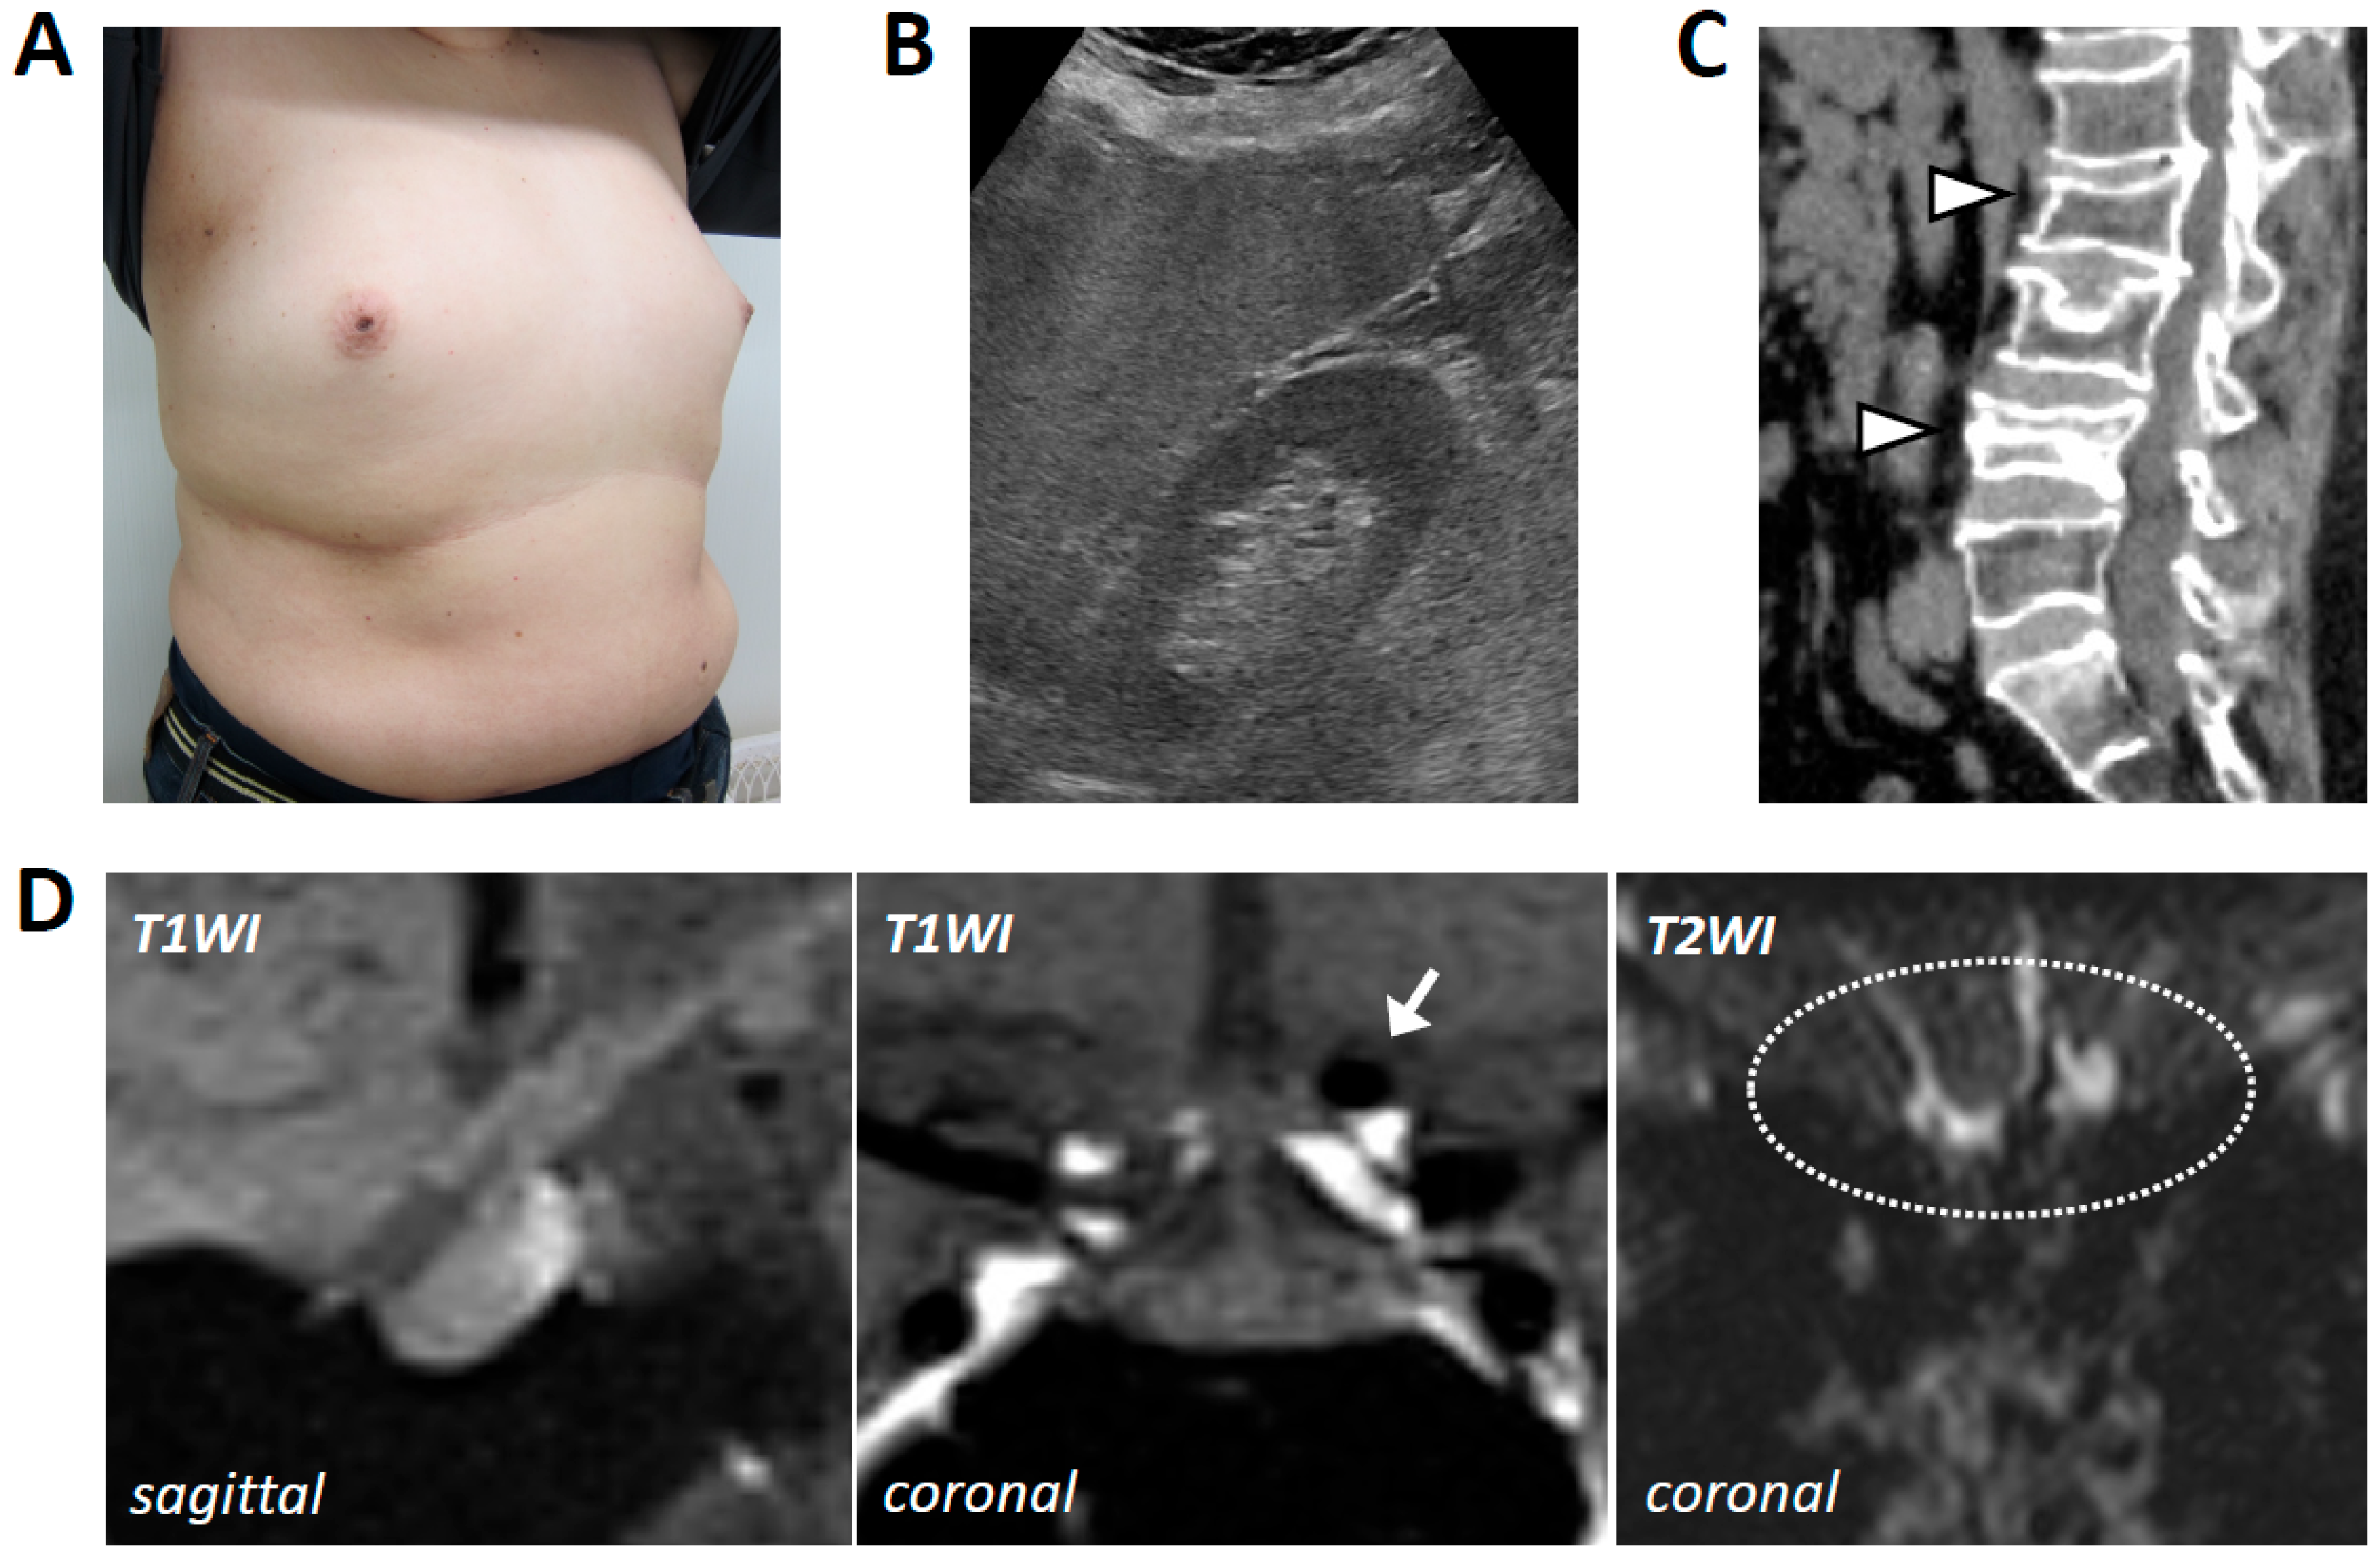

2. Case Presentation